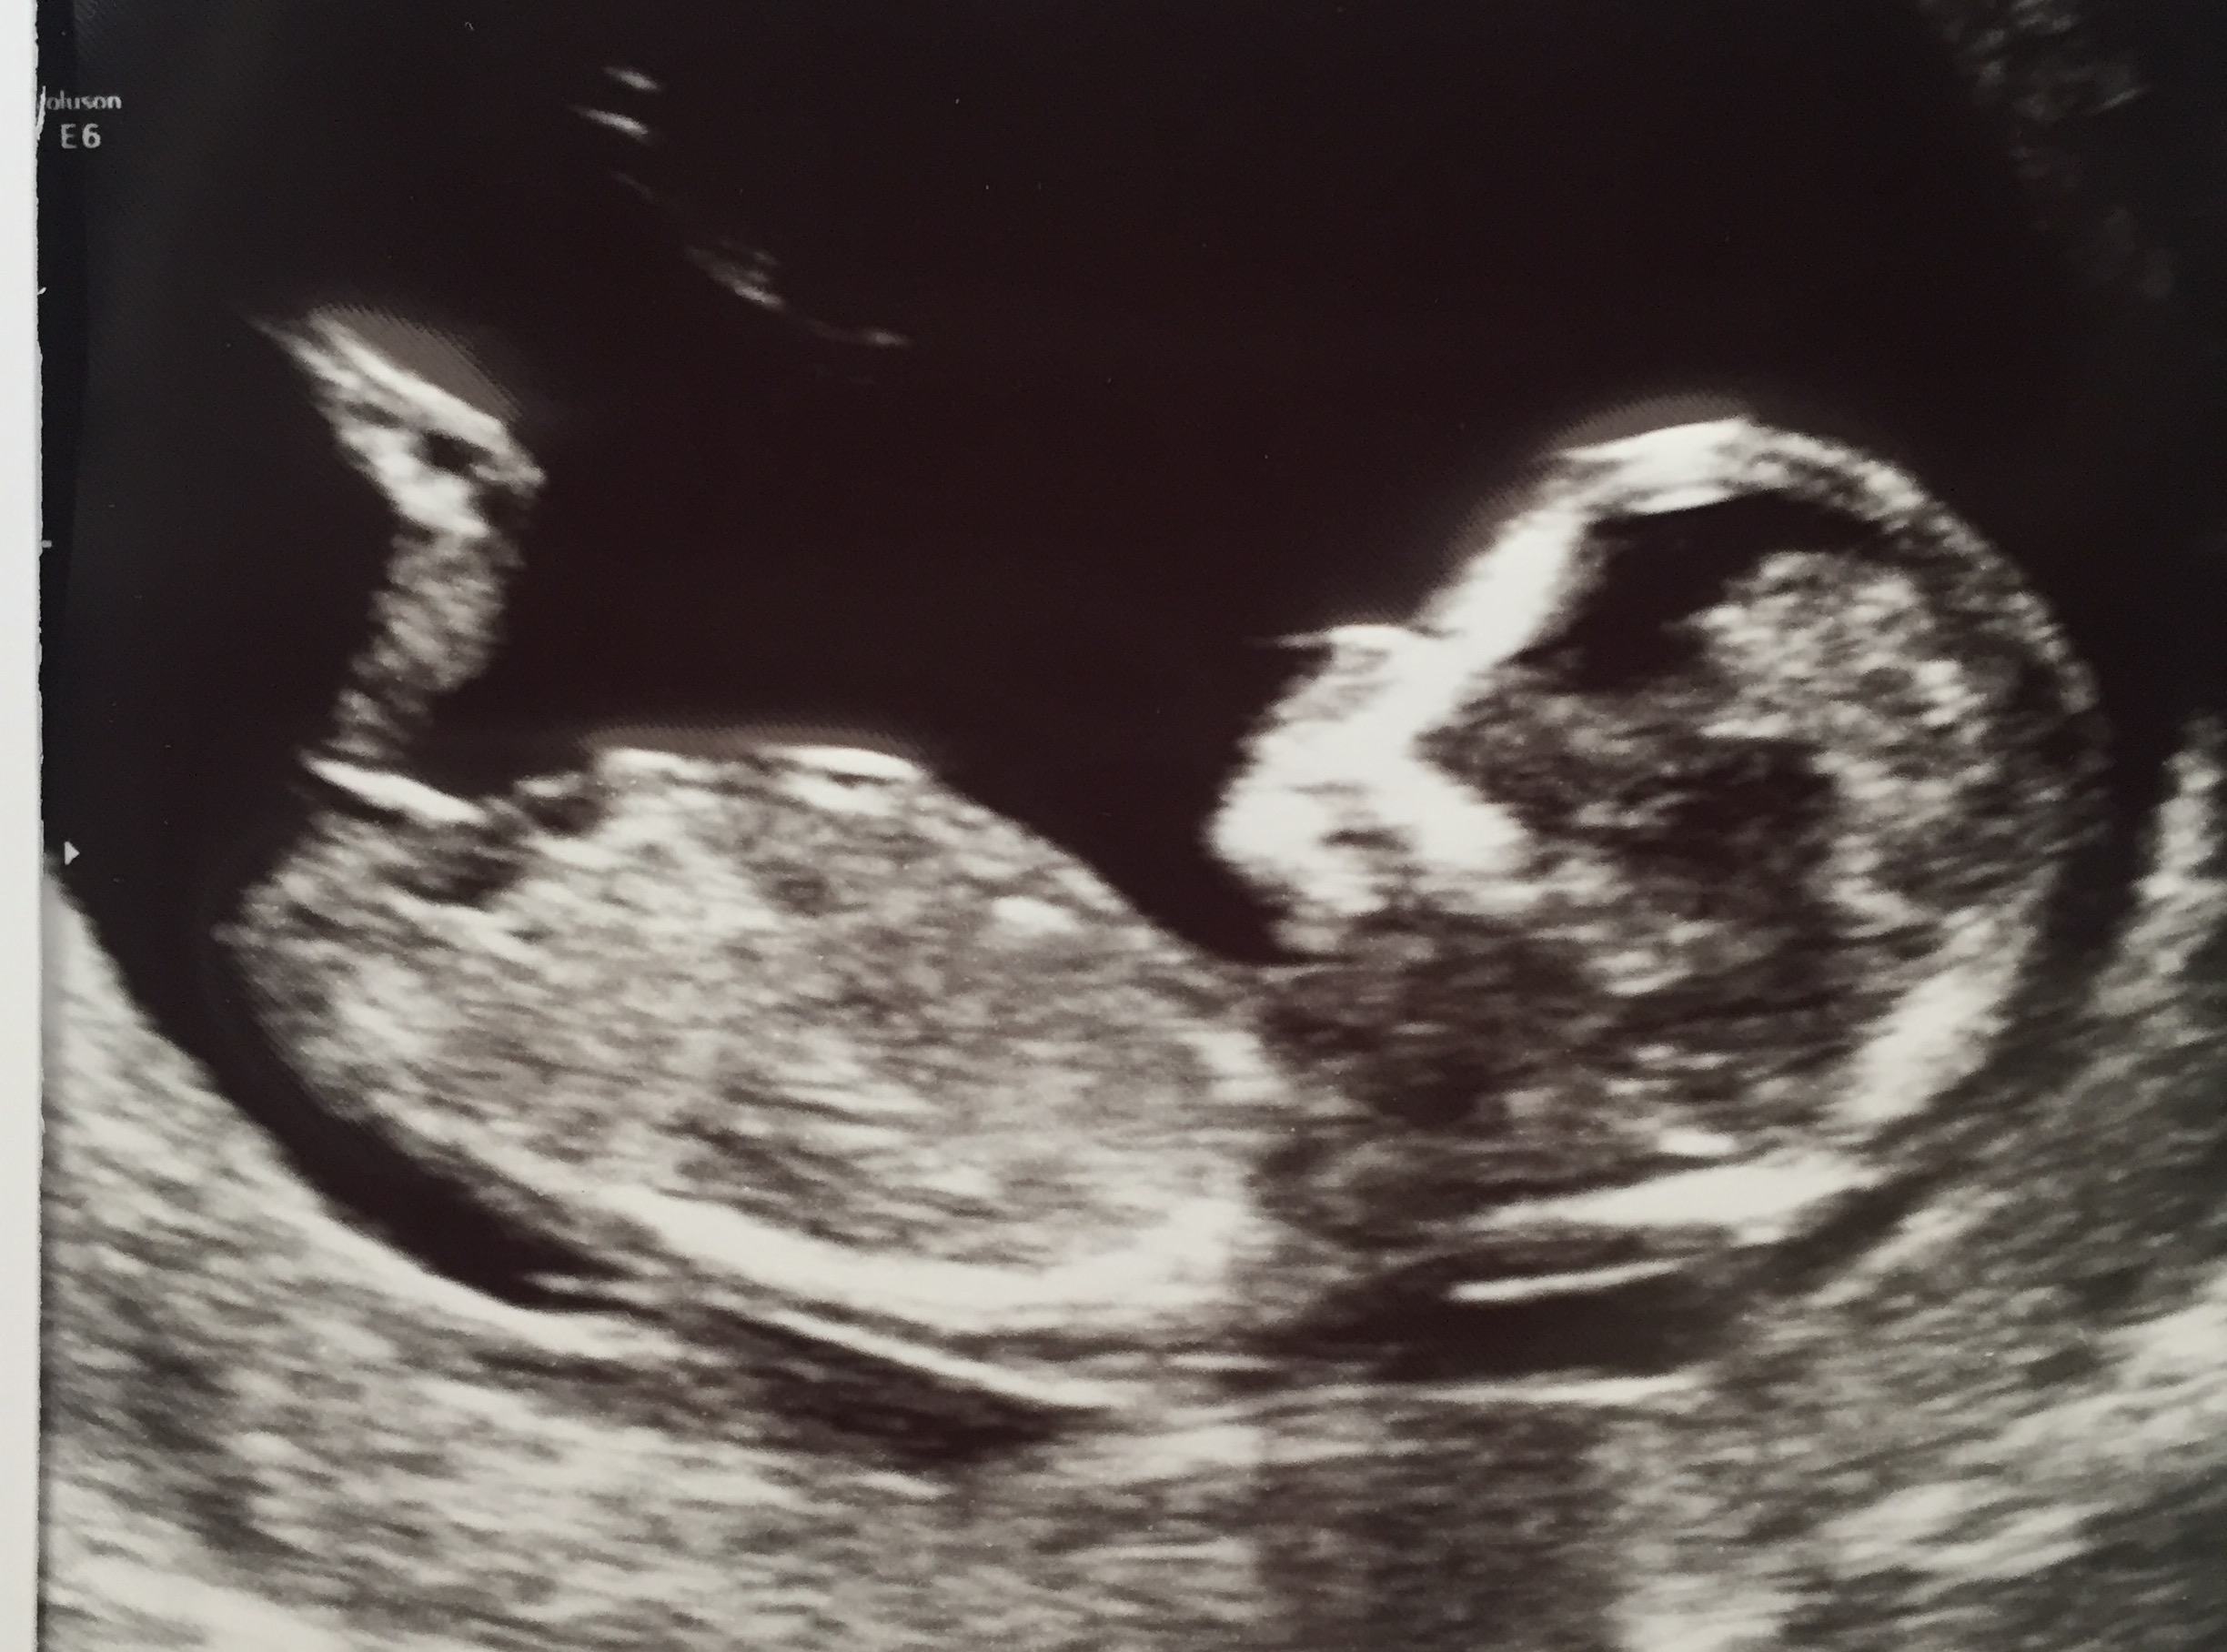

Please can I have any guesses from my scan. Is that white line the nub??

Yes it is. Since it is long, flat, and parallel to the spine, I'm guessing girl [emoji175].